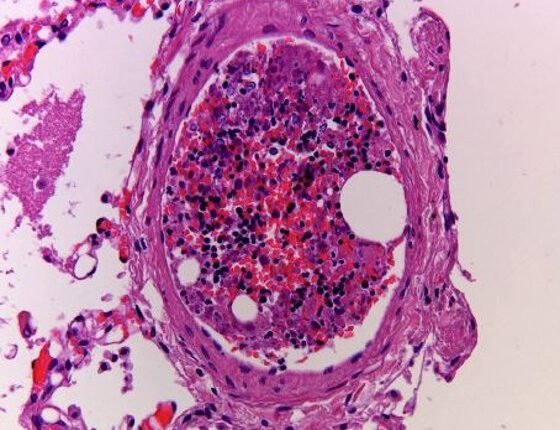

Ο μυελός των οστών είναι ένα μαλακό σπογγώδες υλικό που βρίσκεται μέσα στα οστά. Είναι απαραίτητος για τη μετάβαση που κάνουν τα βλαστοκύτταρα για να γίνουν κάποιος από τους τύπους των κυττάρων του αίματος (ερυθρά αιμοσφαίρια, αιμοπετάλια ή λευκοκύτταρα).

Η νόσος του μυελού των οστών συμβαίνει όταν υπάρχει κάποιο είδος ανωμαλίας ή παρεμβολής στην παραγωγή αιμοκυττάρων. Η λευχαιμία, η απλαστική αναιμία και τα μυελοδυσπλαστικά σύνδρομα (MDS) είναι τρεις τύποι διαταραχών του μυελού των οστών, που επηρεάζουν την παραγωγή των κυττάρων του αίματος και του μυελού των οστών. Τα συμπτώματα κάθε τύπου της νόσου μυελού των οστών ποικίλλουν ανάλογα με τη σοβαρότητά τους, ωστόσο τείνουν να είναι παρόμοια.